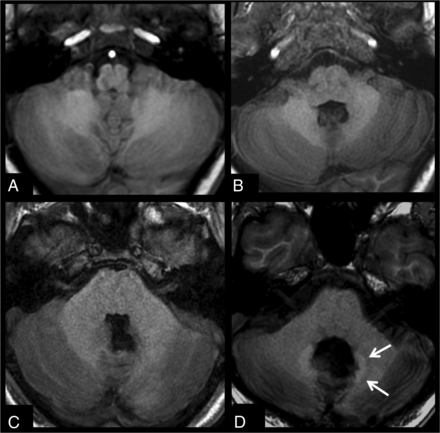

Figure 2 shows a comparison of 2 patients after 20 injections, one with no treatment variables and 1 patient with medulloblastoma after radiochemotherapy. Figure 3 shows images before and after 10 gadobenate dimeglumine injections in a patient with no treatment variables and a second patient with a medulloblastoma, after surgery and radiochemotherapy.

T1-weighted images acquired before (A and C) and after 20 gadobenate injections (B and D) in a patient with follow-up for optic glioma without radiation or chemotherapy (A and B) and a patient with medulloblastoma after an operation and radiochemotherapy (C and D). Subtle signal changes of the dentate (arrows) can be seen in the patient without any therapy, while the patient with RCTX shows distinct T1 signal changes of the dentate and perifocal edema.